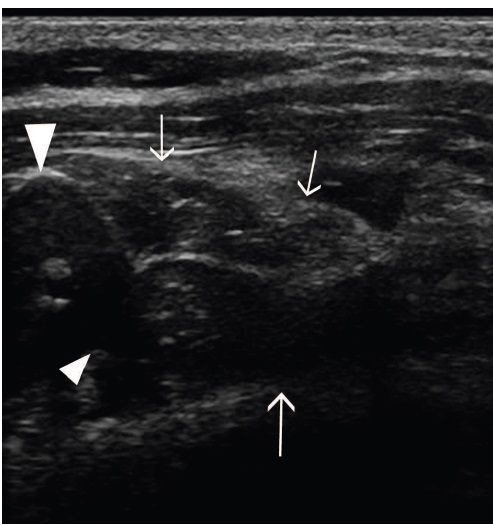

Fig 8: Comparison of echogenicity of the cricoarytenoideus lateralis and vocalis (arrows)

and cricoarytenoideus dorsalis (arrowheads) musculature. Horses with recurrent

laryngeal neuropathy have increased echogenicity and more homogeneous echogenicity

of the cricoarytenoideus lateralis and cricoarytenoideus dorsalis muscles. Dorsal plane

ultrasound images of the cricoarytenoideus lateralis muscle of (a) a horse with recurrent

laryngeal neuropathy and (b) a normal horse. Transverse plane ultrasound images of the

cricoarytenoideus lateralis and vocalis muscles of (c) a horse with recurrent laryngeal

neuropathy and (d) a normal horse. Dorsal plane ultrasound images of the cricoarytenoideus

dorsalis muscle of (e) a horse with recurrent laryngeal neuropathy and (f) a normal horse. In

the dorsal plane images, rostral is to the left and caudal is to the right and in the transverse

plane images, dorsal is to the left of the image and ventral is to the right